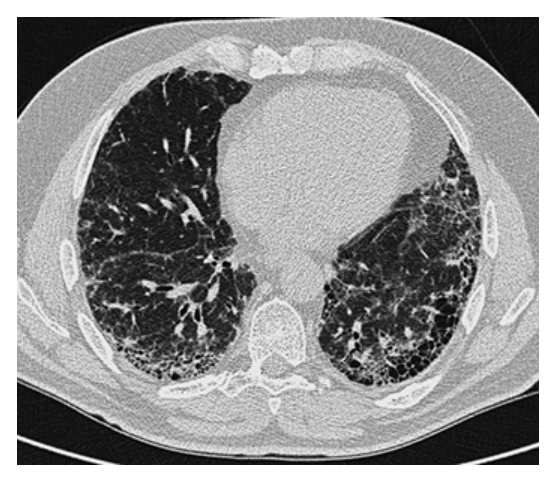

Pulmonary Fibrosis. HRCT of the chest shows honeycombing in the peripheral lung bases with associated traction bronchiectasis.